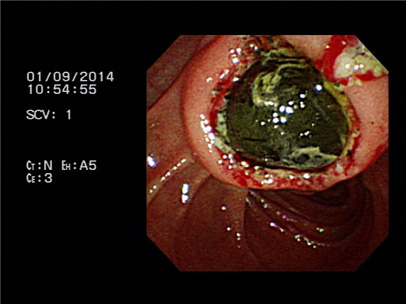

증례 2. 황달로 내원하여 유두부 결석 진단하에 담도내시경을 이용한 결석 제거술 시행 1예.